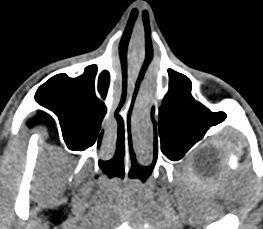

La infecciones profundas, como las que afectan las inserciones de los muculo pterigoideos, son difíciles de valorar, más aún si son incipientes. Es importante estar atentos a los procesos de los senos paranasales, que cuando son incipientes afectan a la grasa de la fosa pterigopalatina y retroantral. La fosa pterigopalatina siempre debe contener algo de grasa.

ESPACIO PAROTÍDEO:

Como el nombre indica, contiene la glándula parótida, la cual puede afectarse por procesos bacterianos (tras la obstrucción de secrecciones) o virales

Hallazgos:

- El lóbulo profundo de la glándula parótida se extiende medial y posterior a la mandíbula.

- Es importante estar familiarizados con densidad normal de la parótida, que debe ser baja comparada con los músculos y alta comparada con la grasa subcutánea tanto en TC sin y con contraste.

- Las infecciones virales suelen ser bilaterales (75%) y simétricas sin tanta repercusión de la grasa.